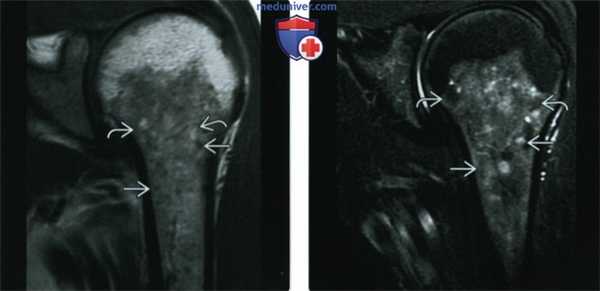

(Слева) МРТ, T1, коронарный срез: у другого пациента с ранее подтвержденным саркоидозом определяются гипоинтенсивные небольшие очаги. Также обратите внимание, что некоторые из этих очагов содержат сигнал от жира.

(Справа) МРТ, Т2, режим подавления сигнала от жира, коронарный срез: у этого же пациента большая часть образований, которые были гипоинтенсивны на Т1, теперь гиперинтенсивны. Тем не менее, эти образования, имевшие жировой сигнал на Т1, теперь визуализируются в режиме подавления сигнала от жира, при котором доказано наличие жировой ткани. Наличие жира внутри некоторых из этих образований свидетельствует о наличии саркоидных гранулем (при соответствующей клинической картине), а не метастазов злокачественной опухоли.